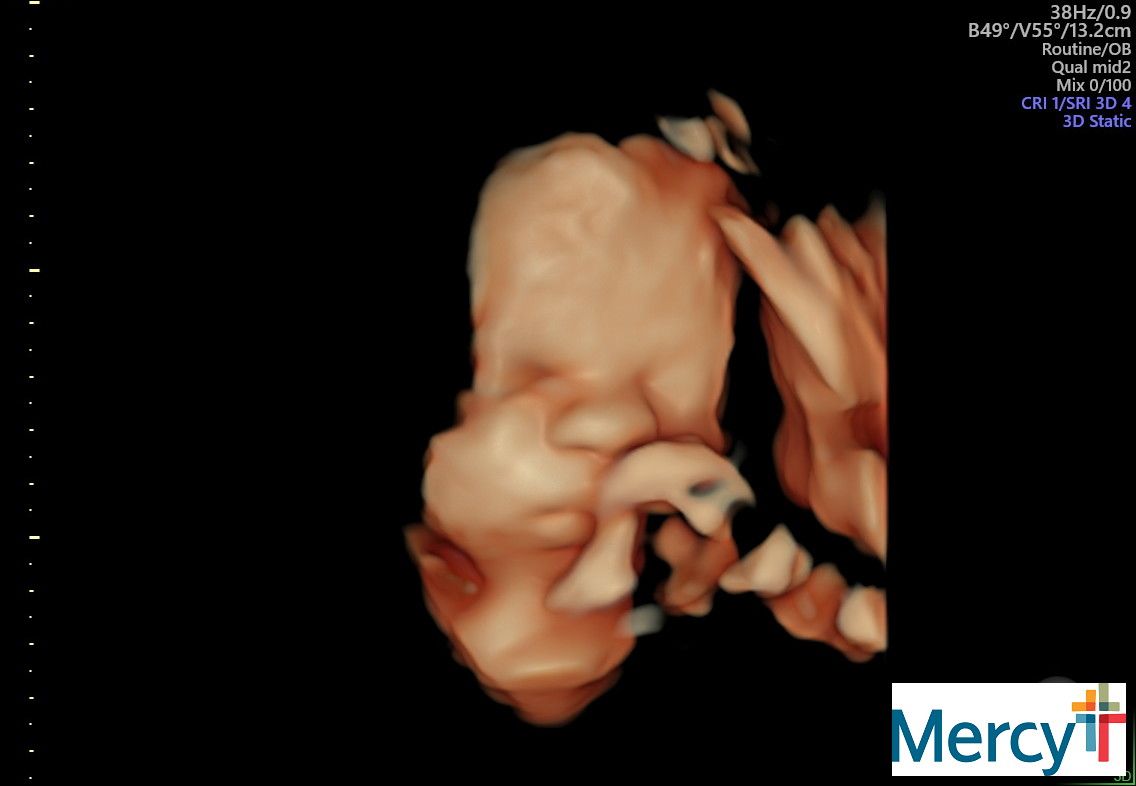

At 32 weeks my appointments would change from once a week to twice a week. These appointments would have a NST (non-stress test) and an ultrasound to check my anniotic fluid levels.

Lupus pregnancies are so complex. The placenta ages rapidly near the end and risk for stillbirth is so high.

She was giving me some more instructions from my MFM doc, and mentioned that because of the high monitoring I needed to be ready to have this baby any time after 34 weeks.